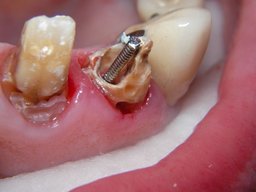

Links nach Wurzelfüllung beim Einpassen des Titanstiftes. Rechts dann der schon provisorisch beschliffene Amalgamaufbau im Zahn 12.

Links das Kontrollfoto nach der Sitzung am 17.2.06. Damit war die Vorbehandlung in diesem Fall abgeschlossen. Am 28.2.06 erfolgte die endgültige Präparation (das "Beschleifen") aller 4 Zähne. Links das Modell, auf dem die Kronen gefertigt worden waren. Rechts kurz vorm Zementieren der Kronen am 13.3.06. Aus der Längendifferenz der Zähne rechts und links kann man darauf schließen, daß die Präparation tief unter dem Zahnfleisch erfolgen mußte.